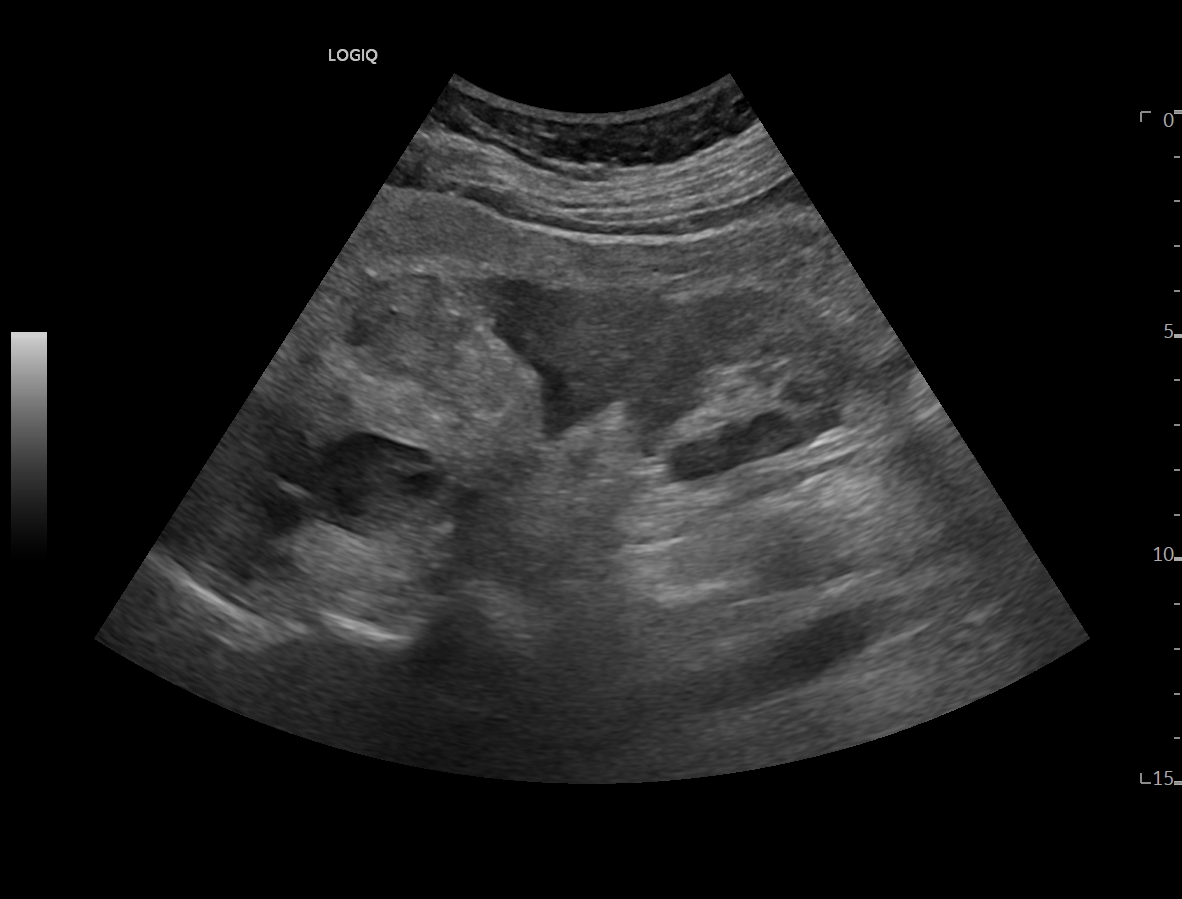

Se realiza ecografía clínica objetivando esteatosis hepática así como litiasis en vesícula biliar que mide 1,6 cm sin signos de complicación. A nivel del riñón derecho presenta lesión hiperdensa en zona media y polo inferior que no capta con realce, sin apreciarse dilatación de cáliz. Se consulta con radiólogo de guardia que indica realizar TAC abdominal para filiar.